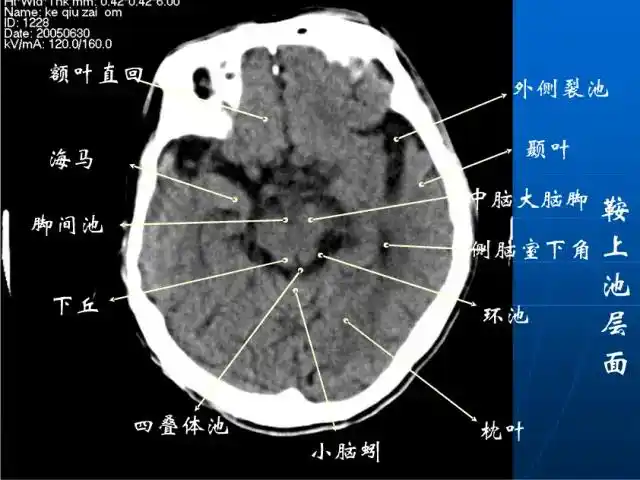

影像医生必须掌握的头颅ct解剖与常见出血梗死判读